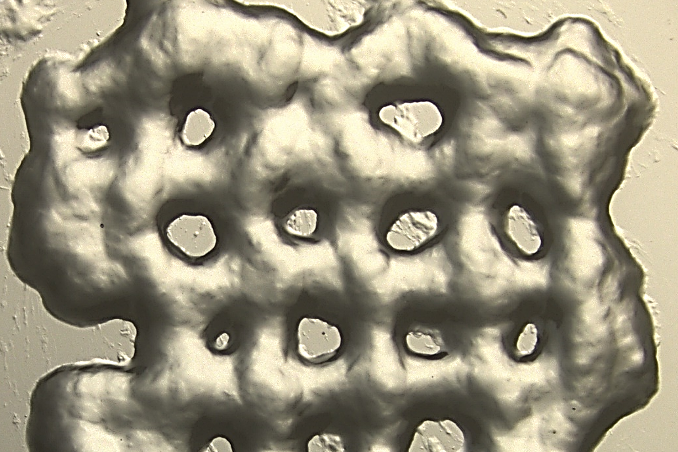

Later, ECMs with weight percentages of 6% wt, 4% wt, and 3% wt were manufactured. The subsequent rheology showed that each ECM needs 200-240 minutes to stabilize. Using scanning electron microscopy (SEM) methods to study these three different formulations, the results revealed the correlation between small amounts of PEG and high porosity.

Further analysis showed that the observed median pore size was 55 μm. Compared with thicker substrates, ECM with this porosity or a lower level is more conducive to cell expansion. As a result, 3%wt hydrogel is considered to be the most friendly to T cell aggregation and proliferation. Then different concentrations of 1 ng/ml, 20 ng/ml and 100 ng/ml CC21 cytokines were added to the ECM mixture to assess the expansion of CD4 T cells.